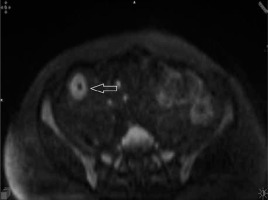

Figure 3

Diffusion-weighted (b = 800 s/mm2) axial image demonstrating high signal intensity due to restricted mural diffusion (arrowhead)